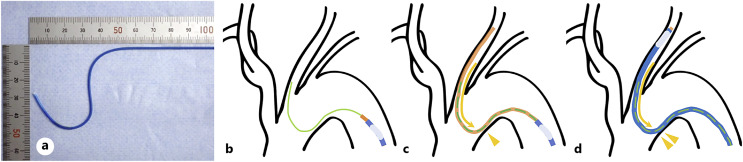

Introduction: During carotid artery stenting (CAS), safe navigation of the guiding catheter (GC) is essential for the success of procedures. However, in cases where stenosis or floating thrombi are located in the common carotid artery (CCA), especially for proximal lesions, advancing the GC without touching the lesions is often difficult. We describe a preliminary experience of the "no-touch" technique for navigating the GC to the CCA using an inner catheter with a specifically designed shape and stiffness optimized to overcome tortuous anatomy.

Methods: We retrospectively reviewed CAS procedures involving the "no-touch" technique for treating stenotic lesions in the CCA. A 4-Fr Newton-shaped stiff catheter was positioned in the CCA. Given its high stiffness and dedicated shape, contact with the lesser curvature of the aortic arch absorbed kickback force. Then, a 6-Fr intermediate catheter and an 8- or 9-Fr balloon GC were coaxially advanced in sequence to the target position without guidewire support, ensuring "no-touch" with the plaques. Patient characteristics, aortic arch type, lesion location, and periprocedural complications were recorded.

Conclusion: The "no-touch" technique with a Newton-shaped stiff catheter is useful and feasible for navigating the GC in treating stenotic lesions in the CCA, particularly with tortuous anatomy, proximal lesions, and vulnerable plaques.